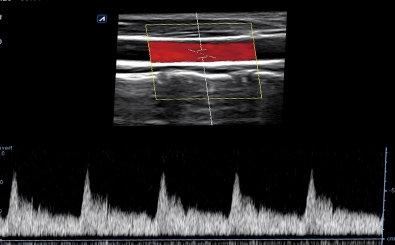

CLINICAL IMAGES

臨床影像

Carotid Artery

Carotid Artery